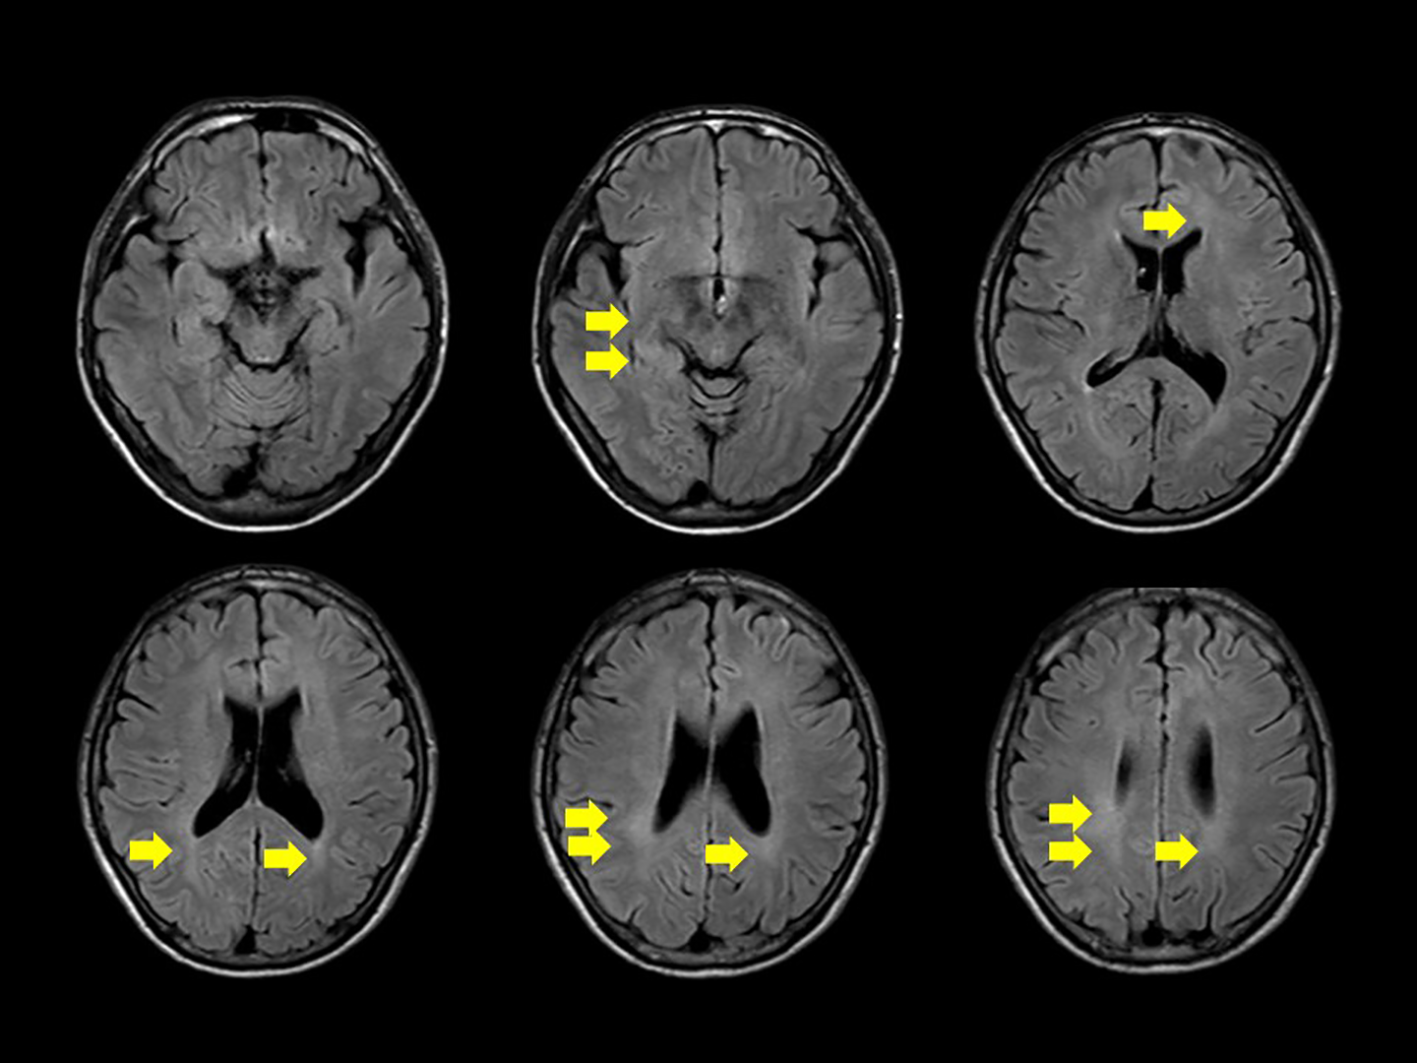

We conducted a comprehensive investigation to determine the cause of visual impairment and elevated inflammatory markers. Brain MRI revealed diffuse faint fluid-attenuated inversion recovery (FLAIR) hyperintensity in the deep white matter. No obvious tumor lesions, pathological enlargement of the ventricles, abnormal signals, or brainstem atrophy were observed. Diffusion MRI showed no infarction, and magnetic resonance angiography did not reveal any considerable stenosis or aneurysms (Figure 1). MRI of the cervical, thoracic, and lumbar spines revealed no substantial abnormalities. According to the cerebrospinal fluid (CSF) analysis, the CSF IL-6 level was 17.8 pg/ml (serum IL-6, 2.6 pg/ml), CSF sIL-2R levels were below commercially available detection sensitivity (<100 U/ml), and CSF cell count was 2/μl (lymphocytes, 2; polymorphonuclear leukocytes, <1). The CSF cultures, including those for acid-fast bacilli and general bacteria, tested negative. Self-adjustment of PSL was not performed, and the patient continued PSL at a dosage of 3.5 mg/day. According to the international consensus recommendation criteria for diagnosing neuro-Behçet disease (5), definite neuro-Behçet disease must meet all of the following criteria: 1) satisfy the International study Group Criteria 1990 or any other accepted current or future criteria for Behçet disease; 2) recognize neurological syndrome (with objective neurological signs) to be caused by Behçet disease and supported by relevant and characteristic abnormalities seen on neuroimaging and/or CSF analysis; and 3) lack of a better explanation for the neurological findings. As a reference finding, it has also been stated that cerebrospinal fluid tests show inflammatory changes such as increases in cells, protein concentrations, and IL-6 levels. In our case, CSF analysis was repeated after a 3-week interval, showing a decrease in the CSF IL-6 level to 6.7 pg/ml. In our patient, CSF and MRI imaging data were not consistent with typical manifestations of neuro-Behçet disease.

Figure 1

Diffuse, faint high signal on fluid-attenuated inversion recovery is observed in the deep white matter on head magnetic resonance imaging (yellow arrow). No apparent signs of meningitis, tumorous lesions, abnormal signals or enhancement, pathological ventricular enlargement, or brainstem atrophy are noted.

Although a diffuse, faint FLAIR hyperintensity was observed in the deep white matter in our patient, no specific findings directly attributable to diplopia were identified on imaging. It is worth considering that the evaluation was not conducted using thin MRI slices, which may have limited the depiction of the lesions. To date, there have been no reports of HA20 cases that specifically mention deep white matter lesions or symptoms of diplopia. The possibility that the sensorineural hearing loss observed during the patient’s clinical course was also a symptom of HA20 was considered. In animal models, chronic neurological inflammation persisted in A20-deficient mice, and the inflammation worsened with age (22). In the present case, the IL-6 concentration in the CSF may have been persistently high. Because the long-term effects of adalimumab on CNS symptoms have not been established, follow-up of clinical symptoms and CSF laboratory findings is important.